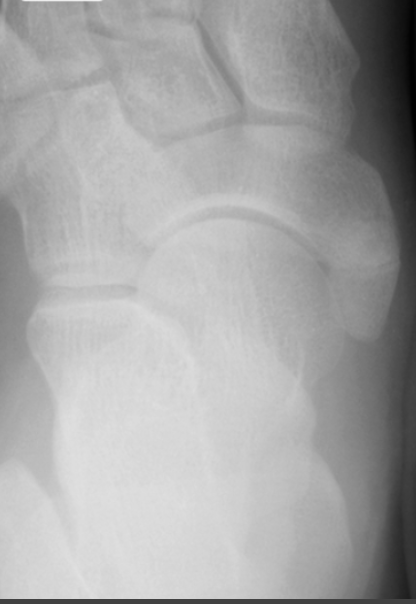

9

Q

What view is this?

A

Lateral Oblique